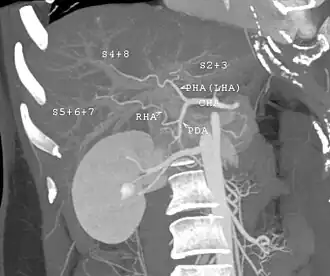

The vast majority of liver transplants use the entire liver from a non-living donor for the transplant, particularly for adult recipients. A major advance in pediatric liver transplantation was the development of reduced-size liver transplantation, in which a portion of an adult liver is used for an infant or small child. Further developments in this area included split liver transplantation, in which one liver is used for transplants for two recipients, and living donor liver transplantation, in which a portion of a healthy person's liver is removed and used as the allograft. Living donor liver transplantation for pediatric recipients involves removal of approximately 20% of the liver (Couinaud segments 2 and 3).

- Before one becomes a living donor, the donor must undergo testing to ensure that the individual is physically fit, in excellent health, and does not have uncontrolled high blood pressure, liver disease, diabetes, or heart disease.[19] Sometimes CT scans or MRIs are done to image the liver. In most cases, the workup is done in 2–3 weeks.